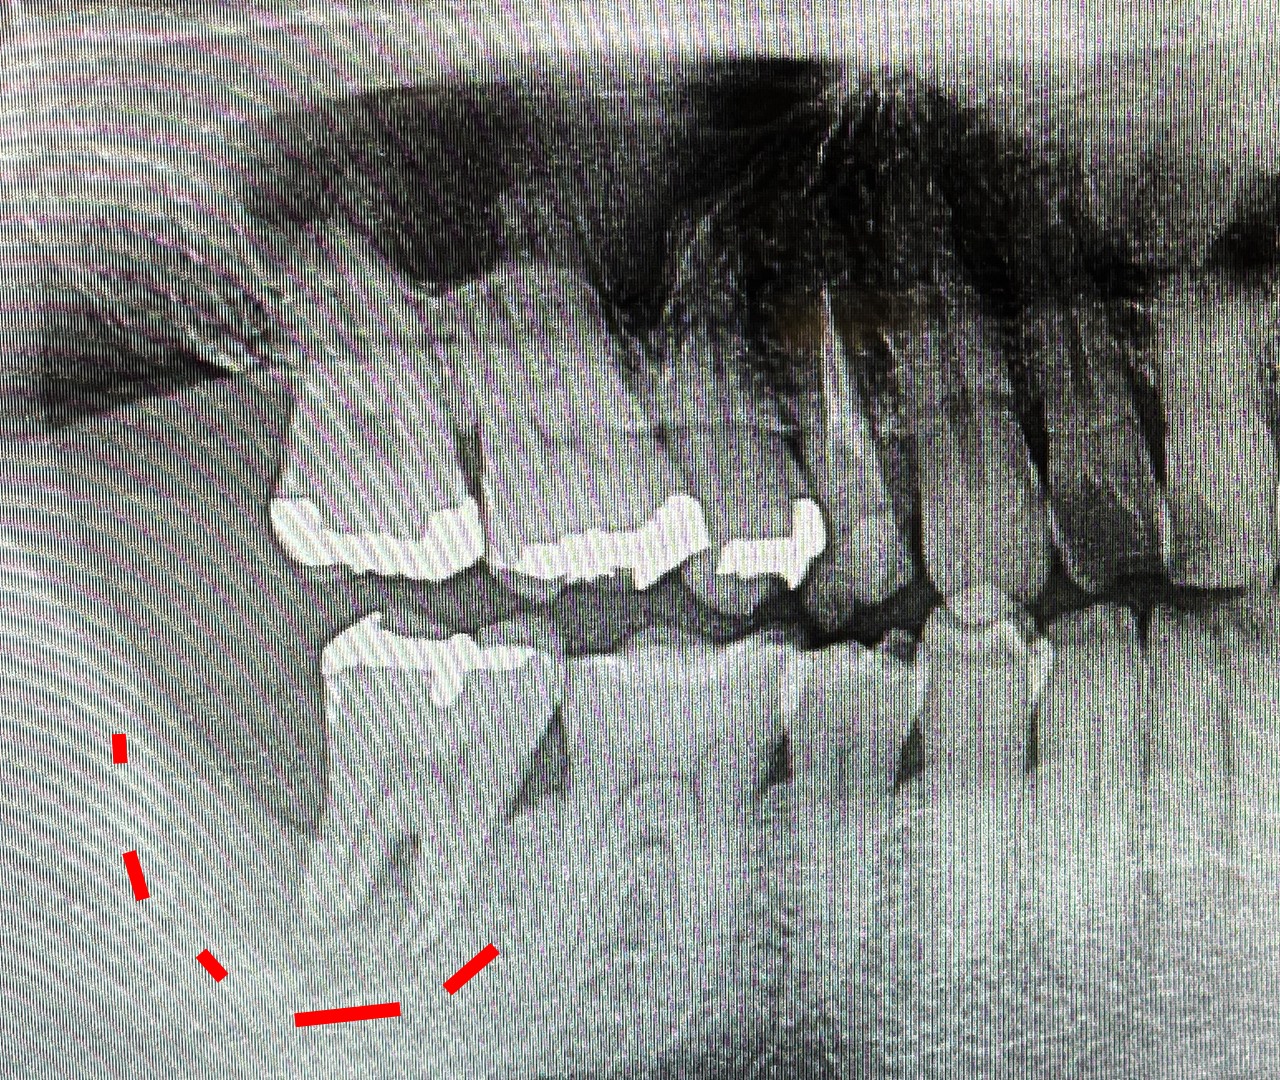

今日は歯医者に行ってから、久しぶりに軽く走ってきた。先日書いた通り色んなところの調子が悪いが、歯科に行って改めて気になっている部分。それはこの歯だ。

まず上の画像。確か2021年の夏に、中小企業診断士1次試験が佳境に入る前に抜いてしまおう、ということで抜いた親知らず。こいつが悪さをした結果が下の画像だ。赤い部分、よく見ると穴がほげている。ここ、実質骨がないので歯が浮いている。こいつに力が加わると痛いし、噛めない。さらにここは空洞になっているようで、ほっておくと歯周病になっていくようだ。それ以外にも歯周病が進みつつあるということがわかったので、色々手を施す必要がありそうだ。しかしこの土台がいない奥歯、インプラントにせにゃならんのだろうなあ。歯医者さんでは、とりあえず抜くと言われているが、もうしばし温存して今後を考えることにする。